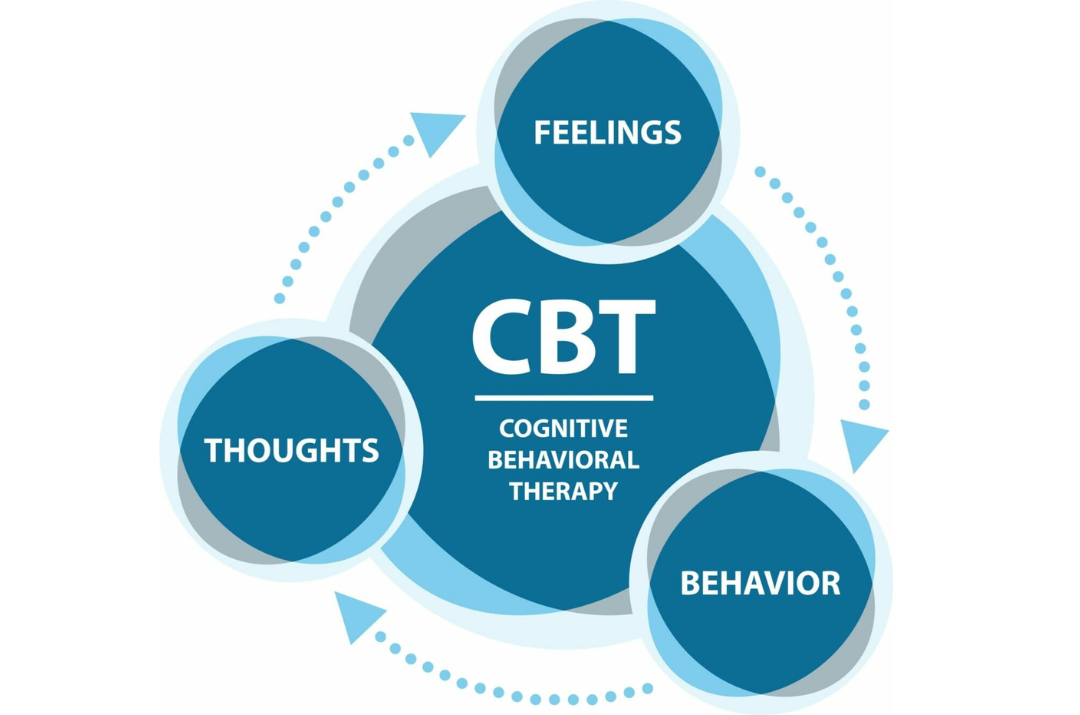

Types of Therapies

Therapies are treatment methods used to improve mental, emotional, or physical well-being. Cognitive-behavioral therapy (CBT) focuses on changing negative thought patterns. Psychodynamic therapy explores unconscious thoughts to address past influences on behavior. Art and music therapies use creative expression for healing. Physical therapy involves exercises to restore movement and reduce pain after injury or surgery.

Types of Therapies

Therapies are treatment methods used to improve mental, emotional, or physical well-being. Cognitive-behavioral therapy (CBT) focuses on changing negative thought patterns. Psychodynamic therapy explores unconscious thoughts to address past influences on behavior. Art and music therapies use creative expression for healing. Physical therapy involves exercises to restore movement and reduce pain after injury or surgery.